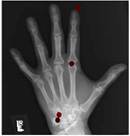

Hand bone age AI

Predict hand bone age. In a small test of 129 random Stanford clinical cases, AI predicted age within 12 months.

C. Fang, S. Baig, D. Larson, M. Fadell, B. Do